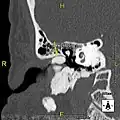

-

Normal ear canal -

Exostosis in ear canal -

Exostosis in ear canal

The normal ear canal is approximately 7 mm in diameter and has a volume of approximately 0.8 ml (approximately one-sixth of a teaspoon).[5] As the condition progresses, the diameter narrows and can even close completely if untreated, although people generally seek help once the passage has constricted to 0.5–2 mm due to the noticeable hearing impairment. While not necessarily harmful in and of itself, constriction of the ear canal from these growths can trap debris, leading to painful and difficult to treat infections.